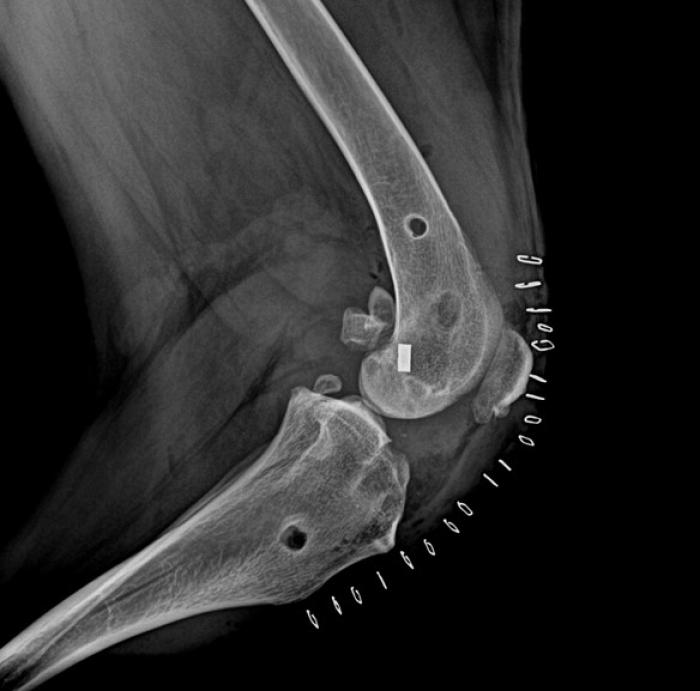

El ligamento de polietileno ultrarresistente de ultra alto peso molecular, se fija mediante tornillos interferenciales de titanio (Figura 2).